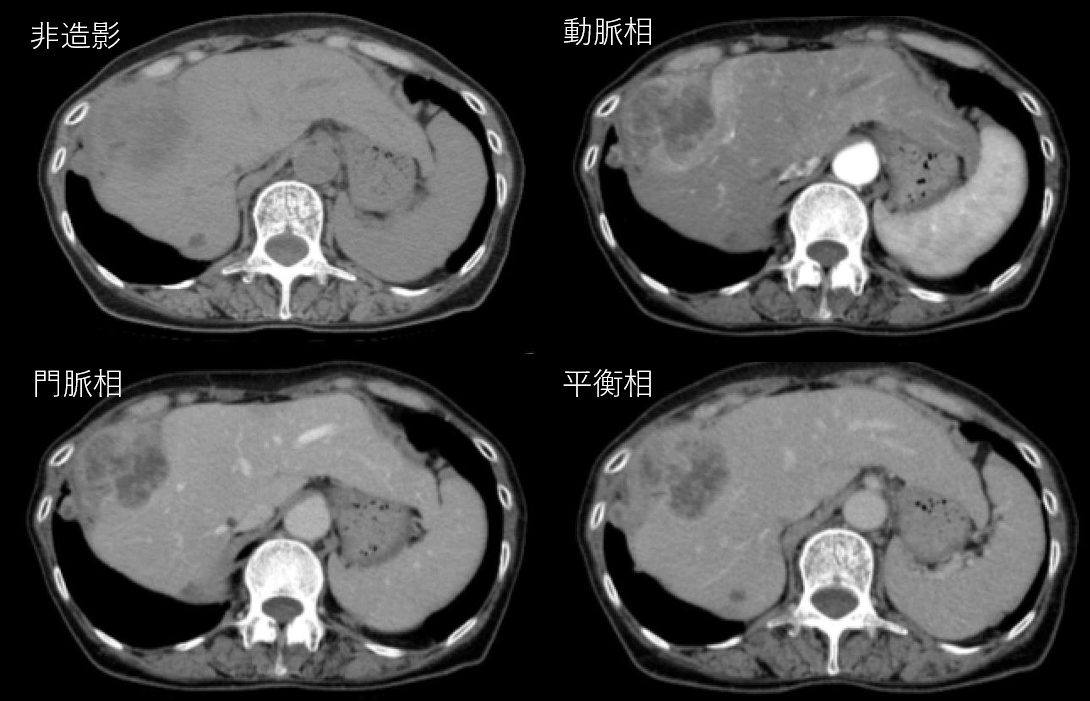

No.122症例2:74歳女性

- 発熱、右季肋部痛

- 近医で超音波検査を施行したところ、肝S8に腫瘤を認めた.